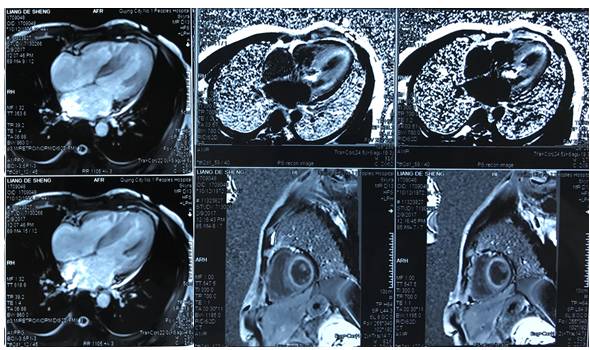

心脏MRI

◆心房扩张,心室增厚

◆镓造影剂延迟强化:弥漫或片状分布,与冠脉分布无关联,心内膜下,心房心室均可见

◆T1 mapping技术:心脏细胞外容积(excellular volume)扩大

◆可评估淀粉样变负担,对预后判断有价值